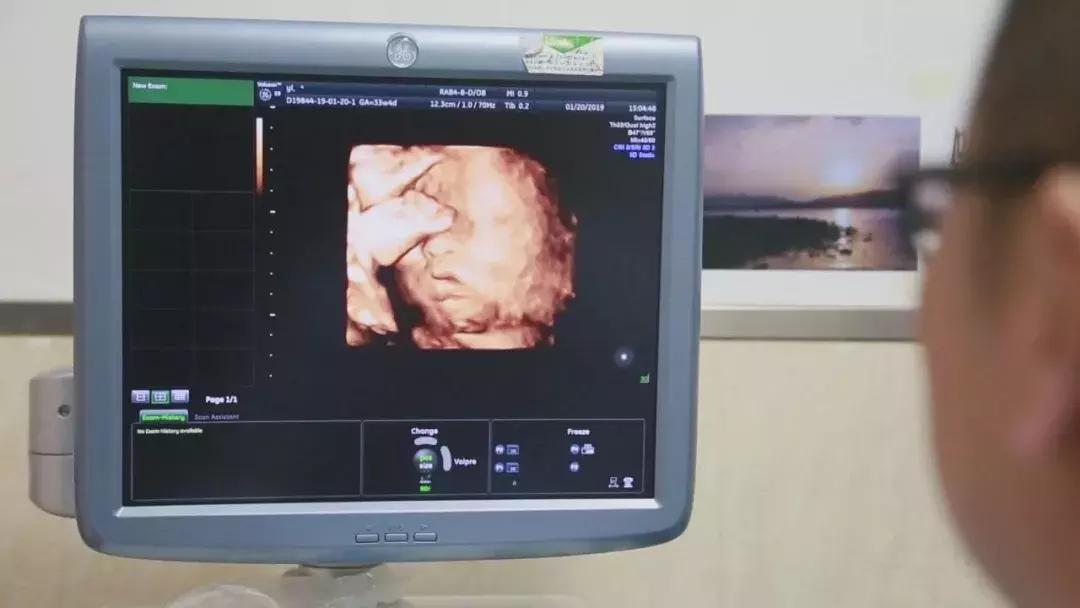

整个孕期,为避免出现并发症、确保母婴健康,妇产科、泌尿外科专家团队结合杨华身体情况,制定了个体化免疫抗排斥用药等方案,并定期进行超声、血药浓度、激素水平等监测。根据监测结果,实时调整用药,保证胎儿羊水、体重、胎心等生长发育指标处于正常范围。

足月的胎儿对移植子宫造成的压力,让分娩的风险成倍增加,陈必良教授团队选择在孕33+6周进行剖宫产手术,迎接这个新生命的到来。2019年1月 20日,陈必良教授主刀施行剖宫产手术,刘朵朵教授配合手术,麻醉科陈敏教授施行麻醉。术中,采取腹壁纵切口完成子宫下段剖宫产,探查确认移植的子宫动静脉缝合口、韧带等恢复良好,手术历时1小时6分钟圆满成功。新出生的宝宝身体各指标正常,体重2kg,身长48cm,Apgar’s评分:1分钟10分,5分钟10分,10分钟10分。剖宫产手术结束后,专家团队没有立即摘除子宫,小两口还计划着孕育二胎。